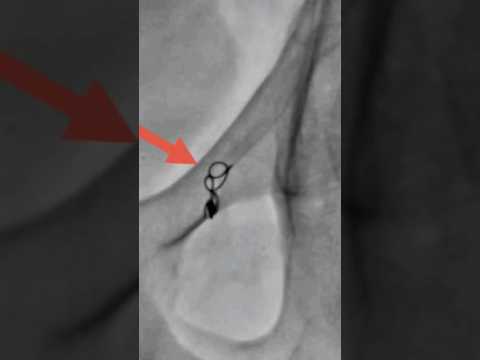

Varicocele embolization live case - Step 7 #nosurgery | Dr. Gaurav Gangwani

Varicocele embolization live case - Step 6 #nosurgery | Dr. Gaurav Gangwani